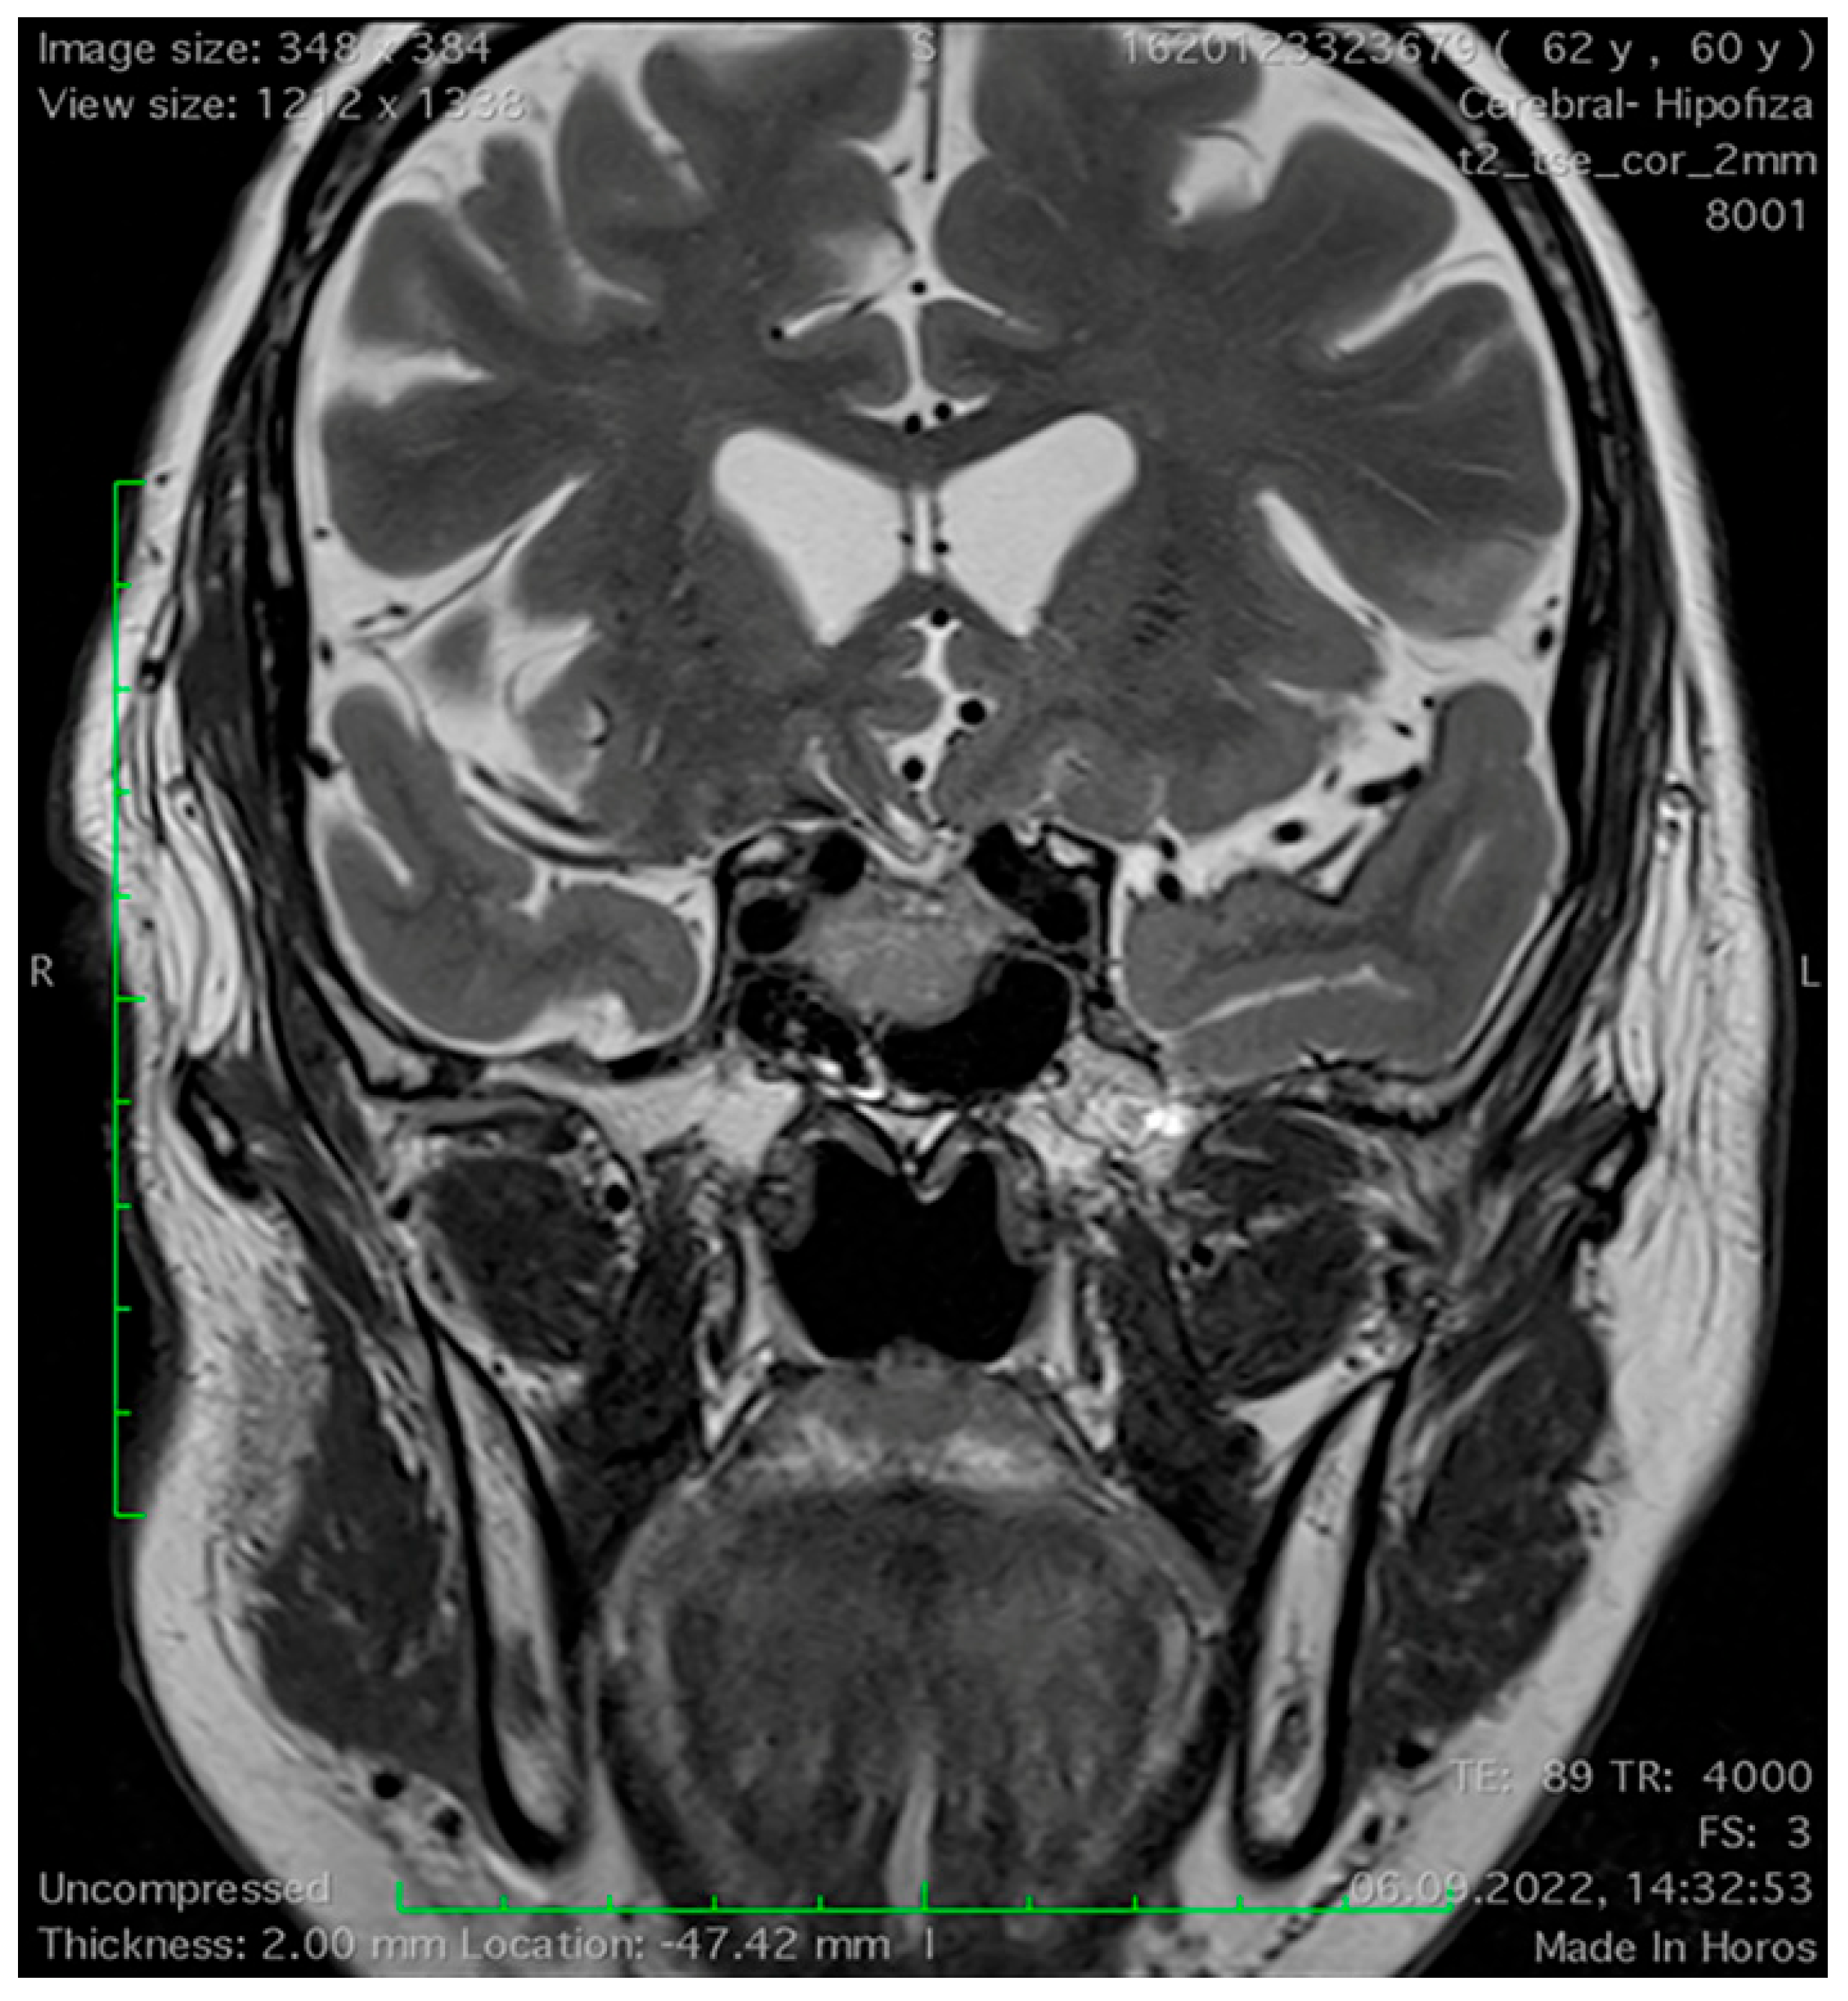

Magnetic Resonance Imaging Features of the Sphenoid Sinus in Patients with Non-Functioning Pituitary Adenoma

2.2. Magnetic Resonance Imaging Study